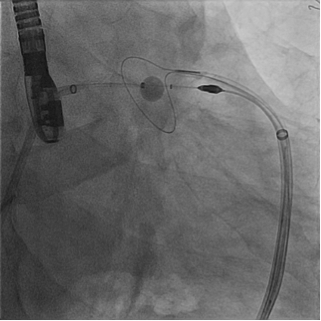

Kevin Jackson uses LARIAT suture delivery device

Kevin Jackson, MD, assistant professor of medicine (Cardiology), recently performed the first left atrial appendage occlusion with the LARIAT suture delivery device at Duke University Hospital.